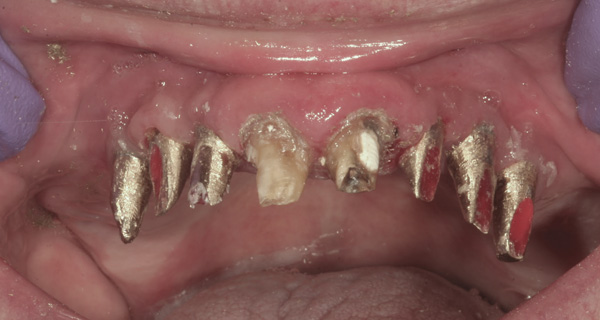

Background: This patient had a failing maxillary dentition and refused to wear a removable prosthesis. A staged approach was employed to retain some of his natural tooth abutments, and recession was noticed at the time of the impression for the second group of implants. Figure 1 shows the patient following insertion of the first set of implant custom abutments; the adjacent natural teeth are still present to support the provisional bridge. Seven months later, as shown in Figure 2, those first-stage custom abutments exhibited evidence of 1 mm to 3 mm of recession.

Results: A decision was made to re-prepare all of the abutments intraorally (Figure 3) so that all abutment margins would be at or below the gingival margin. (Of note, tooth Nos. 8 and 9, also shown in Figure 3, were later submerged for the case to be fully implant-supported.) While re-preparation greatly improved the esthetics of the final result, it required retraction cord placement, new impressions, and new castings.

Figure 3 Abutments re-prepared intraorally.

Figure 3